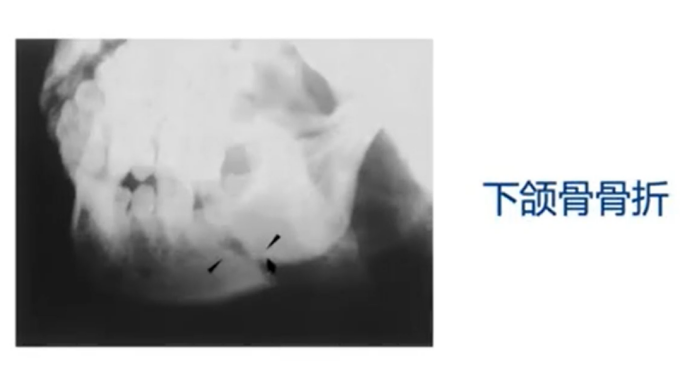

8.颌骨骨折